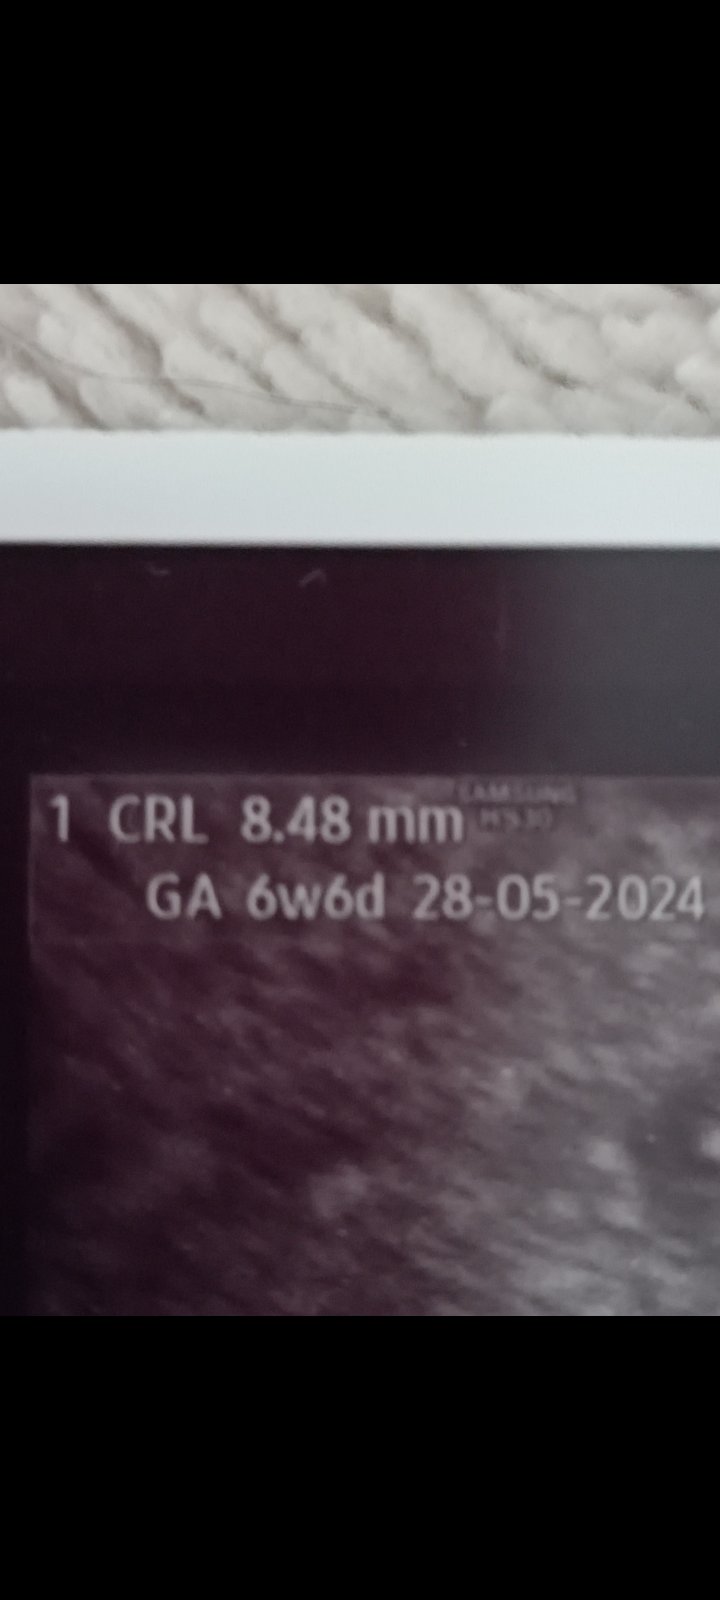

@lenie82 ono to bude asi dobře. Já mám napsáno CRL 8,48mm a 6w6d ... Já zatím nepribiram Estrofem v pondělí začínám vysazovat a zůstane mi do 12 týdne jen 2x amalgen. Jen ty prsa pořád nic.

@eva118 ano. Děkuji 🙏 ❤️ nepíší cm, ale mm.

Jééééé holky, to je asi moje blbost. Já někde pochytila, že to jsou cm. Tak to se omlouvám 🙏